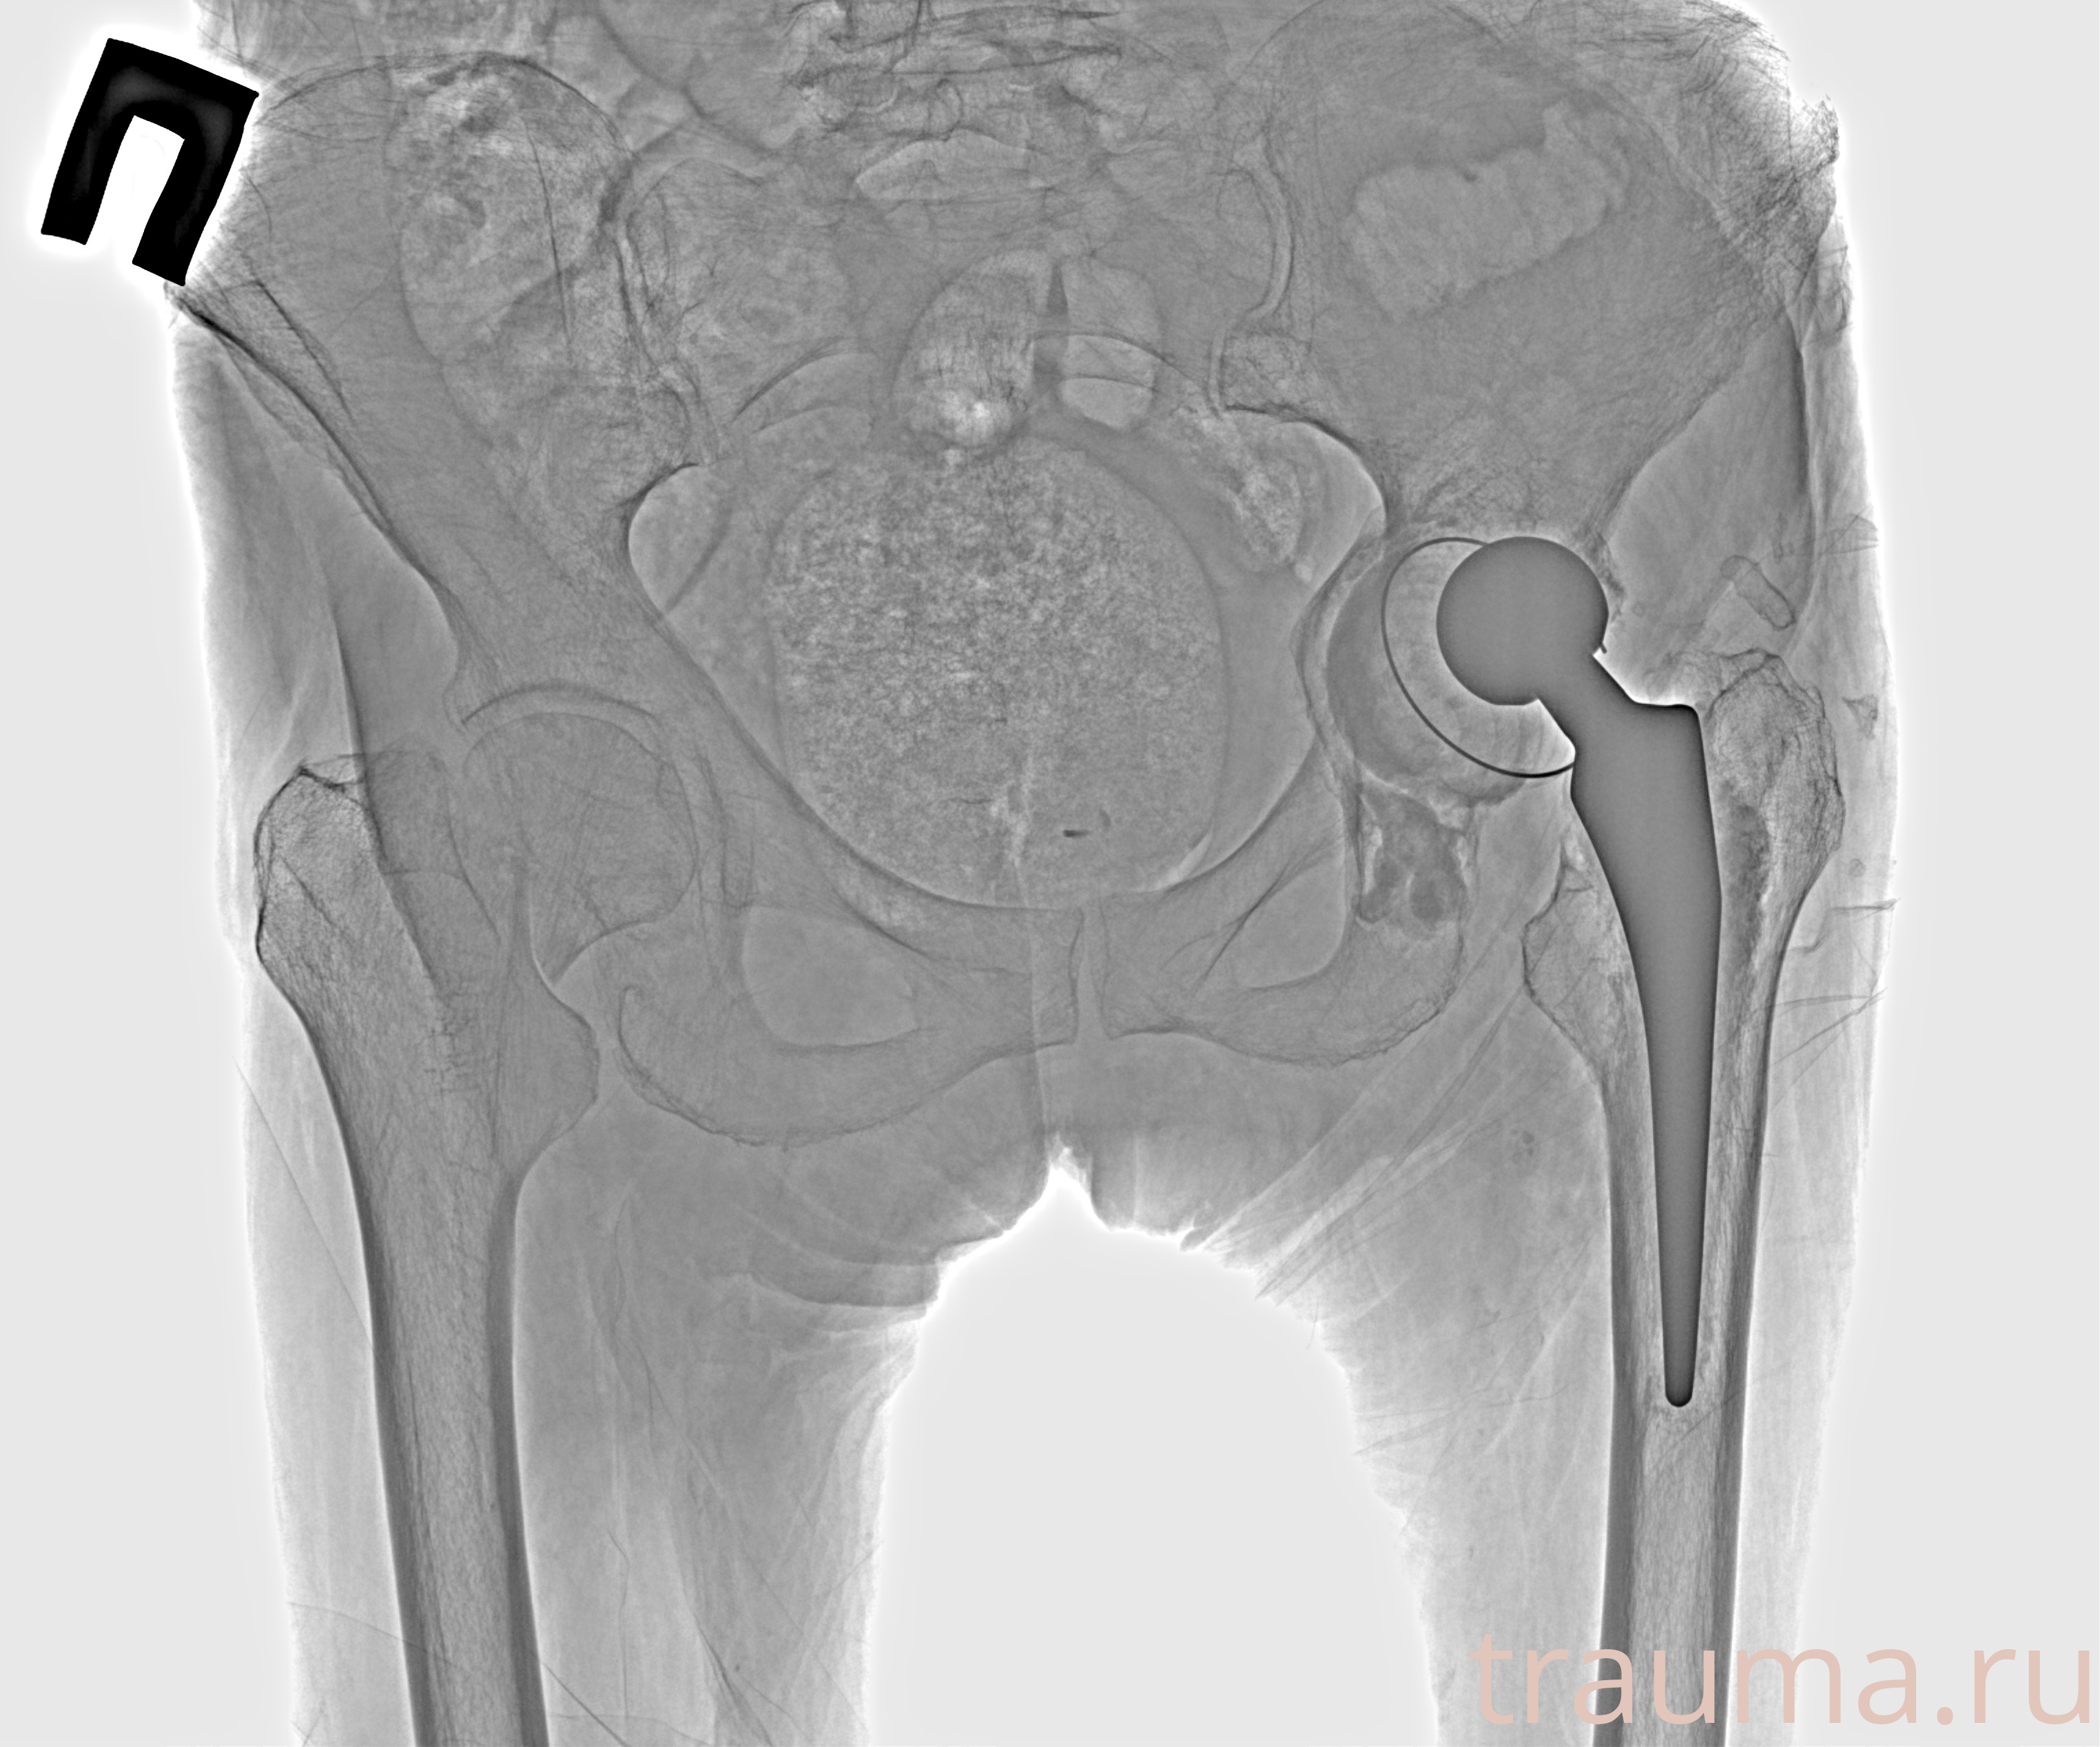

Рентгенограммы

Рентген на дому: по вашему адресу приезжает врач-рентгенолог, травматолог-ортопед с мобильным рентгеновским аппаратом, проводит диагностику травмы или заболевания, делает необходимые рентгенограммы, дает рекомендации по дальнейшему лечению. Получить качественные снимки в домашних условиях возможно благодаря уникальной методике, разработанной МосРентген Центром для института  Склифосовского